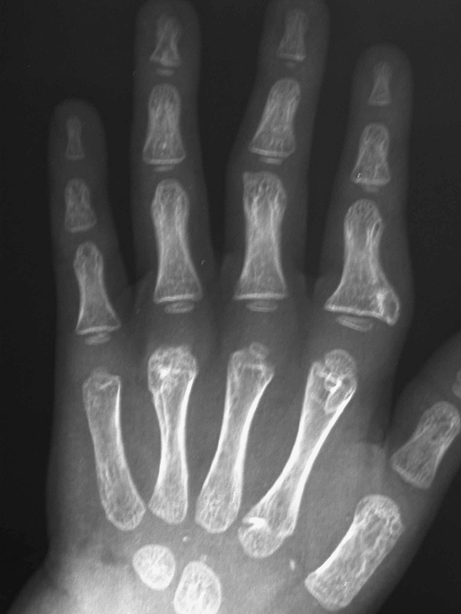

The patient continued to develop more exostoses in the hands, feet, and left clavicle, requiring more surgeries due to symptomatic pain and functional difficulties with finger deviation secondary to the progressive increase in the size of the nodules. (Fig. 2(1, 2)). At 3 years of age, he underwent a second surgery to remove three exostoses from the hand: one from the left index finger at the proximal phalanx (3 mm), a second from the left index finger at the metacarpophalangeal (MP) joint (4 mm), and a third from the left ring finger at the MP joint (10 mm) (Fig. 3). The patient also underwent removal of two exostoses from the lower extremities: one from the right great toe and the other from the left distal tibia above the malleolus.

Fig. 2.

1 A radiograph shows two exostoses: one is on the right great toe, which was resected at the second surgery. The other is on the right medial malleolus, which was resected at the third surgery. 2 A radiograph shows two of three exostoses, which were resected at the third surgery: one on the first web space of the left foot, the second on the left distal tibia

Fig. 3.

A radiograph shows three exostoses on the left hand: one on the index finger at the proximal phalanx, a second from the index finger at the MP joint, a third from the ring finger at the MP joint

He again was symptomatic with his exostosis (Fig. 5(1)). He underwent his fourth surgery at 7 years of age. Six exostoses were removed from the left index finger at the MP joint, the left middle finger at the MP joint, the left ring finger at the PIP and the MP joint, and the left small finger at the PIP and the MP joint (Fig. 5(2)).

Fig. 5.

1 The patient was symptomatic again with six enlarging nodules on the left hand: especially one on the index finger at the MP joint, and two on the ring finger at the PIP and the MP joint. 2 A radiograph shows six exostoses on the left hand, at the index finger at the MP joint, the middle finger at the MP joint, the ring finger at the PIP and the MP joint, and left small finger at the PIP and the MP joint